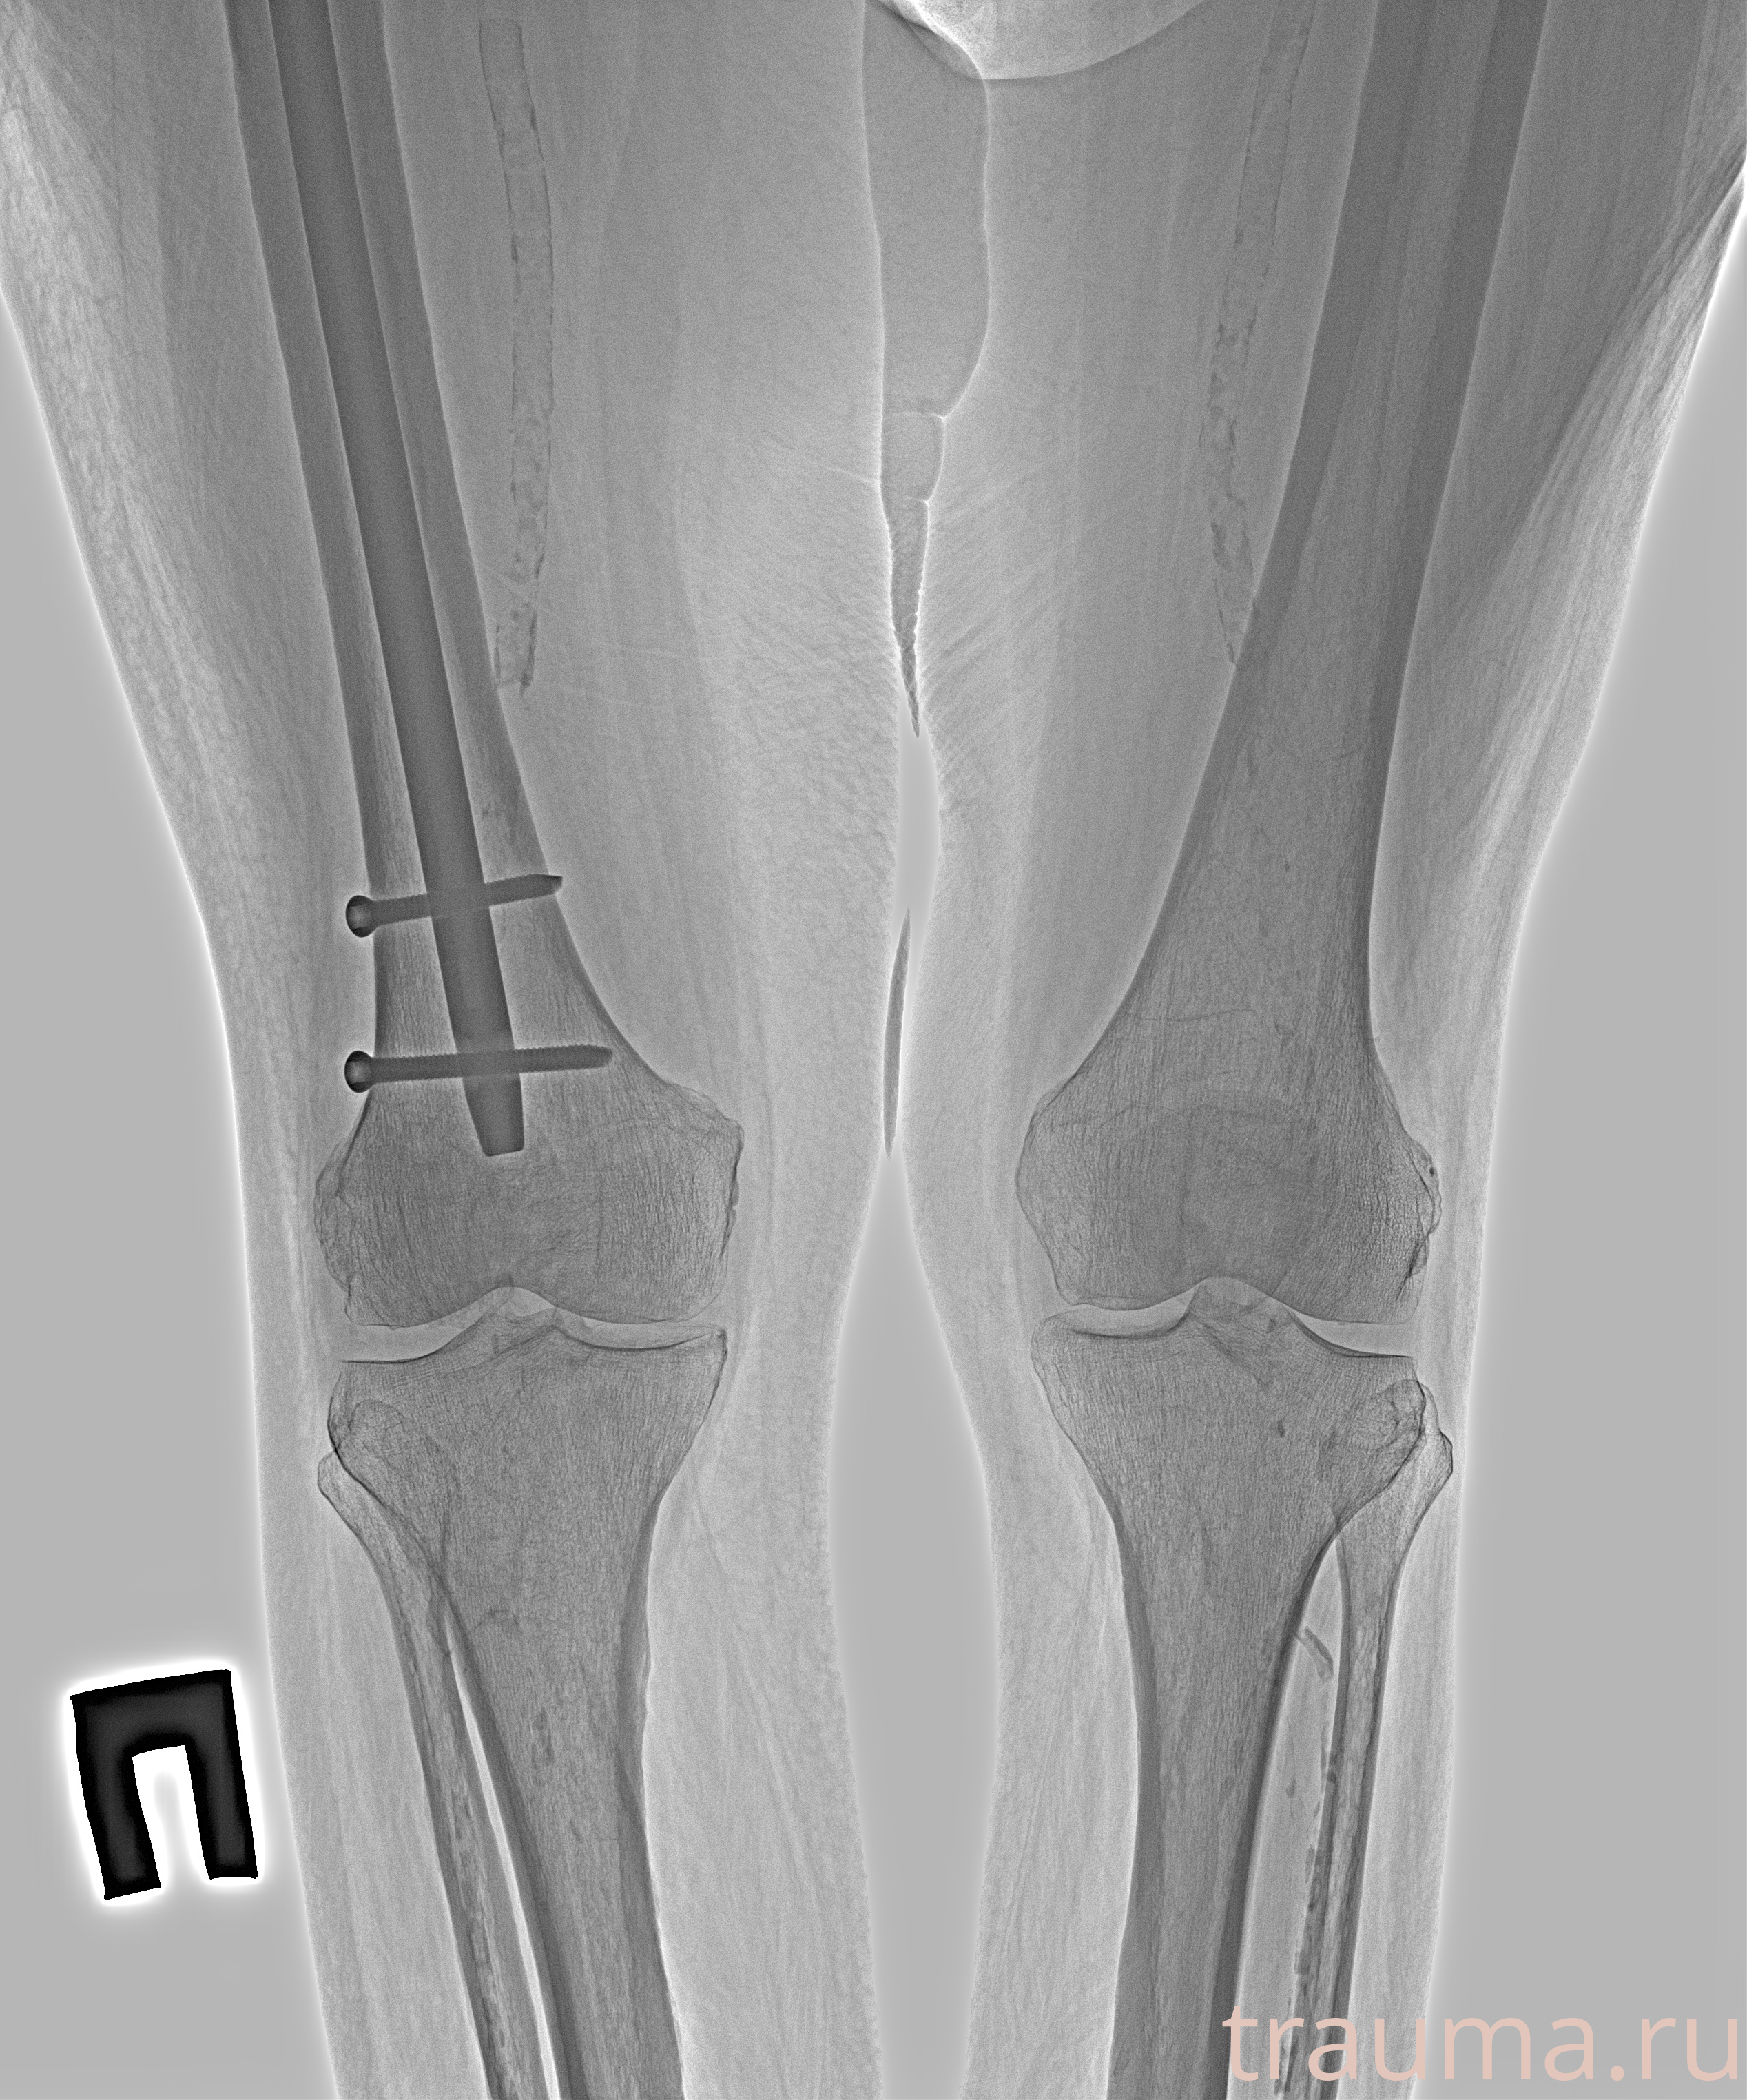

Рентгенограммы